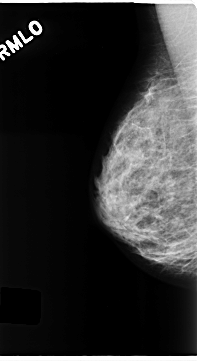

C_0199_1.LEFT_MLO

LEFT_MLO LINES 4704 PIXELS_PER_LINE 2536 BITS_PER_PIXEL 12 RESOLUTION 50 OVERLAY